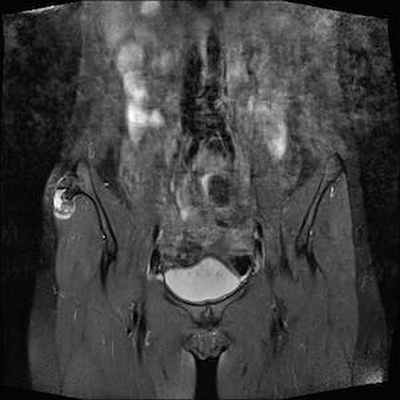

МРТ: чётко видимая хрящевая шапочка, имеющая геперинтенсивный сигнал на T2 (DP)-ВИ и изоинтенсивный сигнал на Т1-ВИ, неправильной формы и очень плотная (23 мм), принимающая дольчатый вид, вызывающая подозрение на саркоматозную дегенерацию. Периферическое повышение сигнала после инъекции.

IRM Pelvis Coronal Pondération DP

IRM Pelvis Coronal Pondération T1gado fat sat